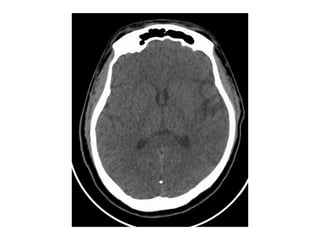

Mme S.Germaine

• 84 ans, retraitée, vit avec sa fille, autonome

• Antécédents:

– Cardiopathie valvulaire

– FA traitéee par antivitamine K (INR < 1,5 8 jours avant

l’admission  augmentation de la posologie)

• Constatation par sa fille, au réveil à 5h00

– Dysarthrie

– Hémiplégie gauche

• Alerte AVC à 6h15

• Arrivée aux urgences à 6h45

• Examen clinique:

– Somnolente

– Déviation réductible de la tête et des yeux à droite

– Hémiparésie gauche

– Anosognosie complète

– NIHSS = 14 (1/0/0/1/2/2/0-2/0-2/0/1/0/1/2)

• AC/FA

• TA = 135/84, FC = 85

• Prélèvements hémostase faits

• Imagerie 7h15

Mismatch diffusion-FLAIR

• Il est 7h30… Attente de

l’hémostase

• 7h45 : INR = 1,47

• Thrombolyse intraveineuse faite aux

urgences

• Evolution clinique:

– Amélioration du déficit neurologique à la fin

de la thrombolyse

– Examen neuro 2 heures plus tard:

• Déficit moteur distal de la main gauche

• Déficit du membre inférieur gauche (chute avant 5

secondes)

• Quadranopsie inférieure gauche

• NIHSS à 2